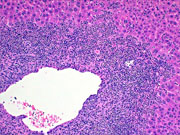

Another example of myelodysplasia from a Tg.AC mouse on a FVB background, treated with rotenone.